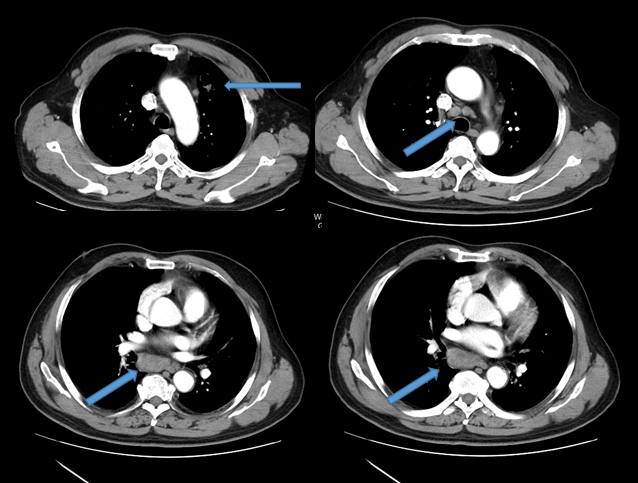

患者后续完善头部增强MR,考虑颅内多发转移瘤(图1)。胸部增强CT见空洞影,璧不均,空洞璧实性部分强化,纵隔淋巴结肿大(图2)。于2019年3月8日行CT定位下肺穿刺,病理检查提示:见恶性肿瘤细胞,非小细胞癌,结合免疫组化,符合腺癌。免疫组化:CK7(+)、TTF-1(+)、CK广(+)、P40(-)、CD68(-)、Vim(+)、Ki67(+,20%)。

image001.png

图1.患者基线时头部增强MRI(2019年2月26日)

图2.患者基线时胸部增强CT(2019年3月7日)